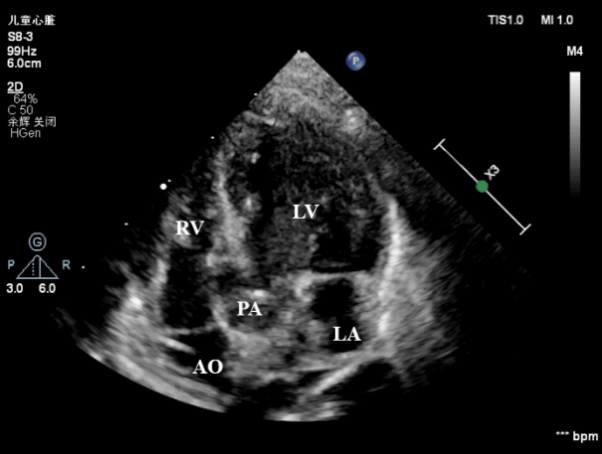

7月19日上午11点40分,孕妇通过剖腹产生下一名体重不到6斤的男婴,出生后宝宝由于缺氧全身呈蓝紫色,呼吸微弱,身体各项指标非常差。心血管超声医学科王斌主任立即床旁急诊超声检查,心脏超声提示:内脏、心房正位,左位心,心室右袢,房室连接一致,心室与大动脉连接不一致,室间隔完整的完全性大动脉转位(S.D.D),细小动脉导管未闭(双向分流),左、右心室发育尚可(见下图)。

心室与大动脉连接不一致:左室与肺动脉连接,右室与主动脉连接(LA:左房;LV:左室;RV:右室;AO:主动脉;PA:肺动脉)